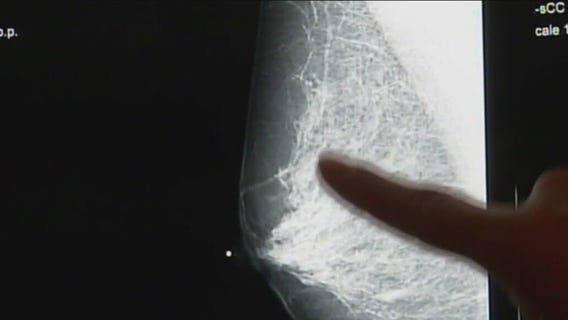

Roseland Hospital expands mammography facilities to improve breast cancer survival chances

Roseland Hospital on Chicago's Far South Side celebrated National Breast Cancer Awareness Month by focusing on more than just raising awareness.